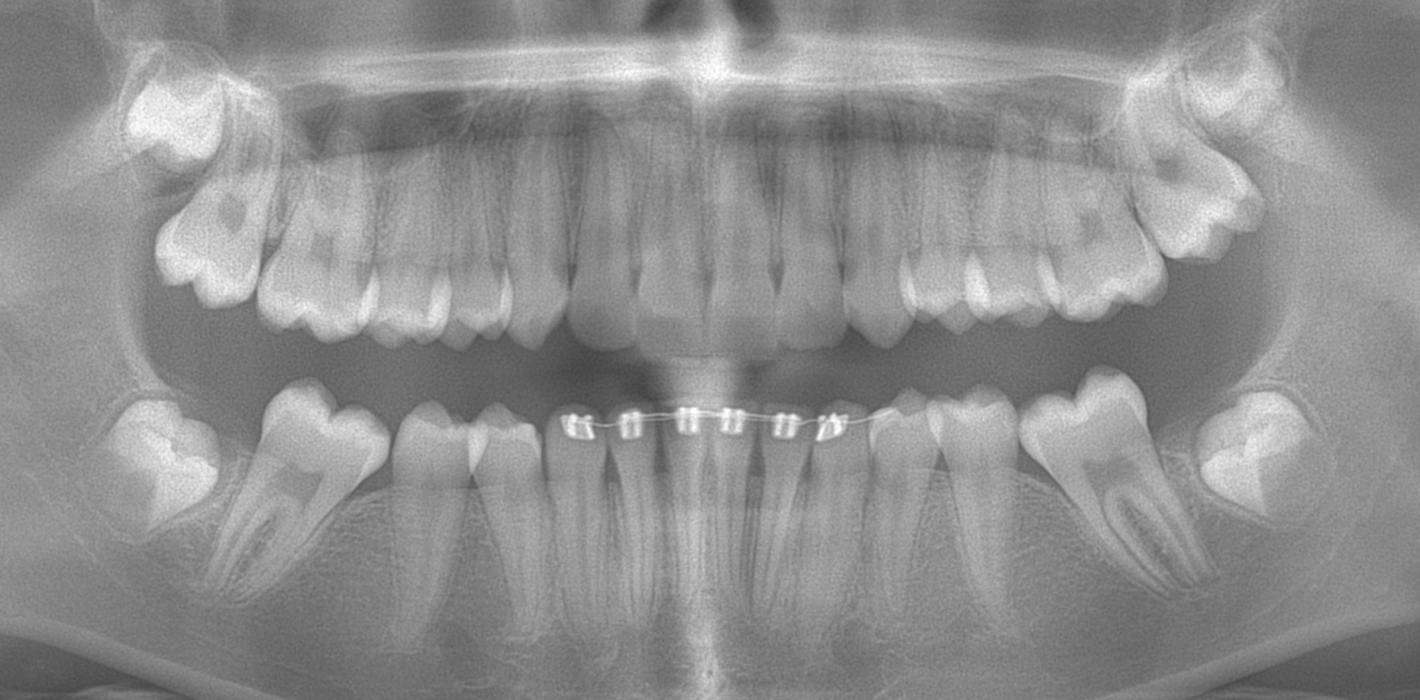

Eine Patientin stellte sich im Alter von neun Jahren erstmals vor. An den ersten Molaren des Unterkiefers wurden vom Hauzahnarzt eine MIH diagnostiziert (Abb. 1a) und die Zähne als nicht erhaltungsfähig eingestuft. Die beiden ersten Molaren wurden hemiseziert und der distale Anteil extrahiert. Gut zu erkennen ist auf dem OPG die annähernd achsengerechte Mesialisierung der zweiten Molaren sowie die Aufwanderung der Zahnkeime der dritten Molaren (Abb 1b: ca. 1,5 Jahre nach Hemisektion). Noch vor Durchbruch der zweiten Molaren in die Mundhöhle wurde auch der mesiale Anteil entfernt. Der spontane Lückenschluss erfolgte innerhalb der nächsten anderthalb Jahre (Abb. 1c). Die endgültige Achsstellung kann nach Ausdehnung der Teilmultibandapparatur eingestellt werden.

Auch wenn nach dem Minimalschadensprinzip meist der Zahnerhalt anzustreben ist, können die Begleitumstände eine Extraktion rechtfertigen. Der Hauszahnarzt übernimmt in der Regel eine Schlüsselrolle im Entscheidungsprozess und der möglichen Einbeziehung von Fachzahnärzten. Erfahrungsgemäß treten insbesondere im Unterkiefer Komplikationen in Form von Alveolenkollaps und der sich daraus entwickelnden Nebenwirkungen auf, welche es zu vermeiden oder zu verhindern gilt. Bei der Indikation zur Extraktion eines Unterkiefermolars sollte eine Hemisektion in Erwägung gezogen werden. So kann mit wenig Aufwand ein achsengerechter Spontandurchbruch der zweiten und dritten Molaren erreicht werden. Sollte die Entscheidung zu einem späteren Zeitpunkt getroffen werden, kann auch hier durch eine Mesialisationsmechanik (Abb. 2c) eine körperliche und achsengerechte Einstellung erreicht werden. Gut zu erkennen ist in Abbildung 2, dass der dezente frontale Engstand weiterhin besteht und keine Distalisierung der Frontzähne oder Prämolaren stattgefunden hat. Spätere Extraktionen mit Komplikationen können vermieden werden. Bisher hat diese Indikation zur Hemisektion (MIH) noch keinen Eingang in den Bema gefunden. In Hinblick auf ein verbessertes Lückenmanagement mit geringeren Risiken, verkürzten Behandlungszeiten, geringerem apparativen und finanziellen Aufwand sollte eine Anpassung zukünftig diskutiert werden. Falls der dritte Molar angelegt ist, wird in vielen Fällen ein Lückenschluss mit Einordnung der zweiten und dritten Molaren möglich sein, sodass am Behandlungsende ein adultes Gebiss mit 28 gesunden Zähnen vorliegt.